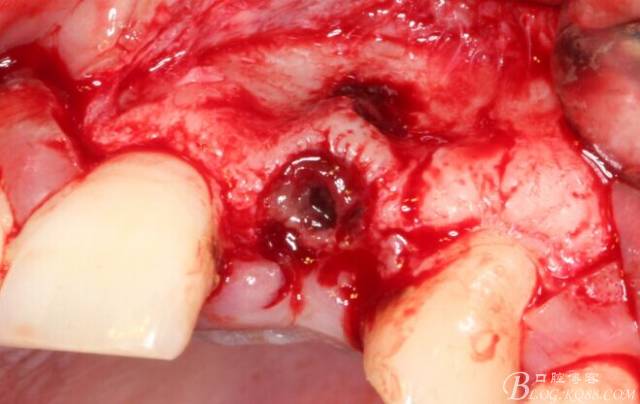

于是我果斷告知患者,手術(shù)失敗了,不能拖延,如不及時(shí)處理,炎癥繼續(xù)發(fā)展會(huì)很快波及鄰牙牙槽骨?;颊呓邮芪业慕ㄗh。切開(kāi)翻瓣,骨粉及生物膜消失了,骨吸收嚴(yán)重,幸運(yùn)的是,因?yàn)樘幚砑皶r(shí),鄰牙骨支持依然存在。

徹底掻刮。

有老師問(wèn)我,為什么不在此時(shí)同期植骨同期植入植體?我的觀點(diǎn)是:不要一次做太多事情,做得越多風(fēng)險(xiǎn)越高。再說(shuō),此時(shí)軟組織不健康,沒(méi)有健康的軟組織如何能保證GBR的成功?所以,我僅放了一塊膠原蛋白就縫上了。